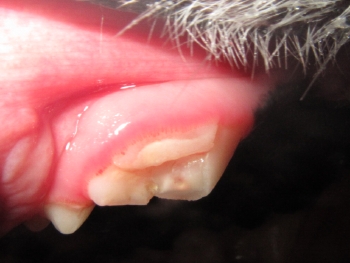

● 歯の破折 3 : 根先膿瘍の放置による目の下の開放創

根先膿瘍は放置することで目の下に穴が空くことがあります。

この3枚の写真に示されるように①は根先部に膿瘍が認められます。②は膿瘍部分に黄色く色づけをしてみました。③は逆サイドの正常な写真になります。![]()